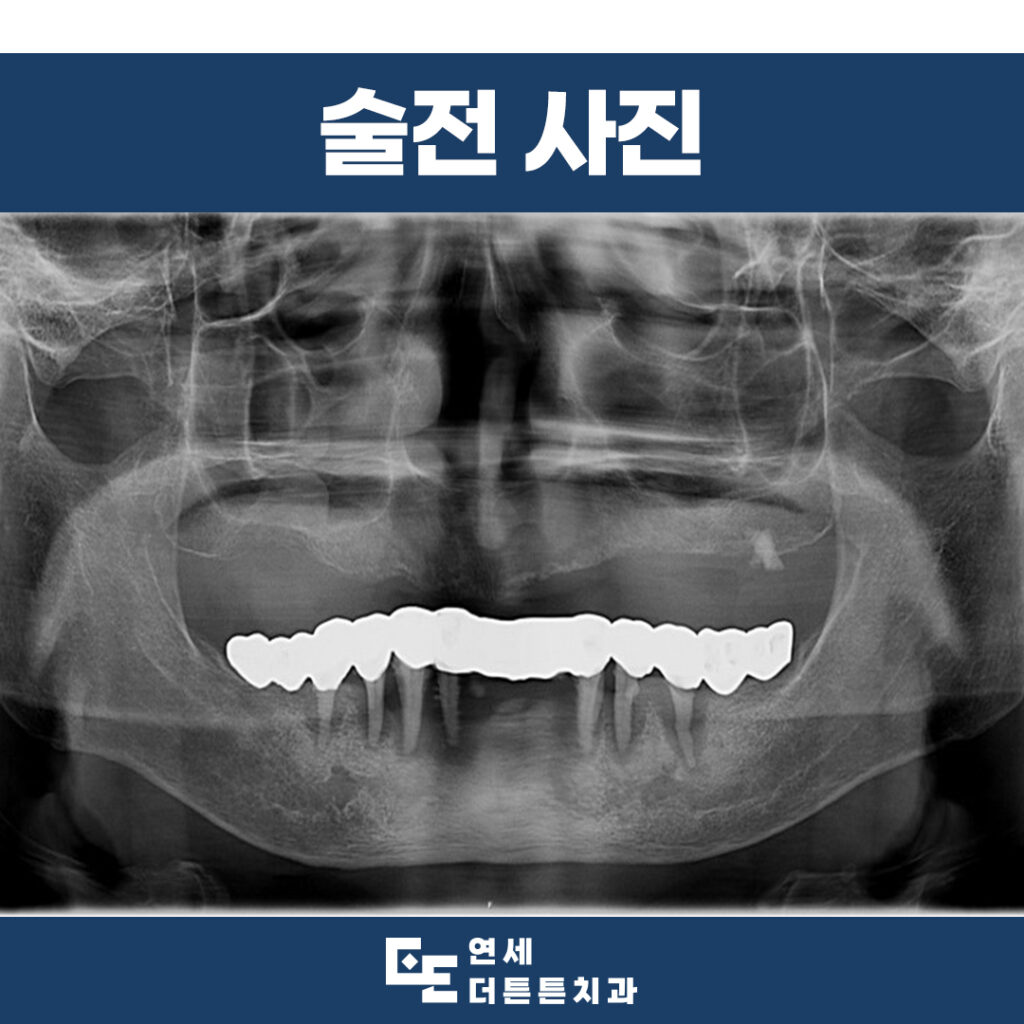

환자분은 70대 여성분으로

기존에 사용하던 임시 틀니의 불편함으로

최종 틀니 제작을 위해 내원해 주셨는데요.

1년 전, 내원 당시 본원에서 다수의 치아를

발치하고 위쪽 임시 틀니를 제작하셨습니다.

진단 결과, 현재는 위, 아래

완전 무치악 상태였으며

다양한 치료 방법에 대해

충분한 설명을 드렸으나

환자분의 사정에 의해 위, 아래

완전 틀니를 진행하기로 하였습니다.